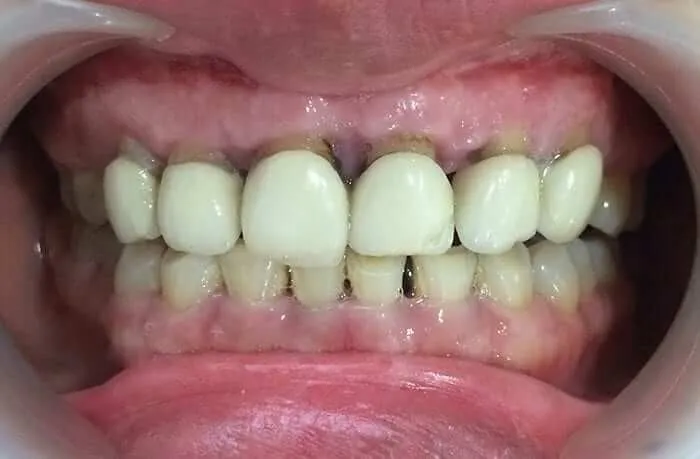

Một số trường hợp muốn bọc răng sứ nhưng điều kiện lợi không cho phép thực hiện. Lúc này, việc cắt lợi sẽ được thực hiện trước